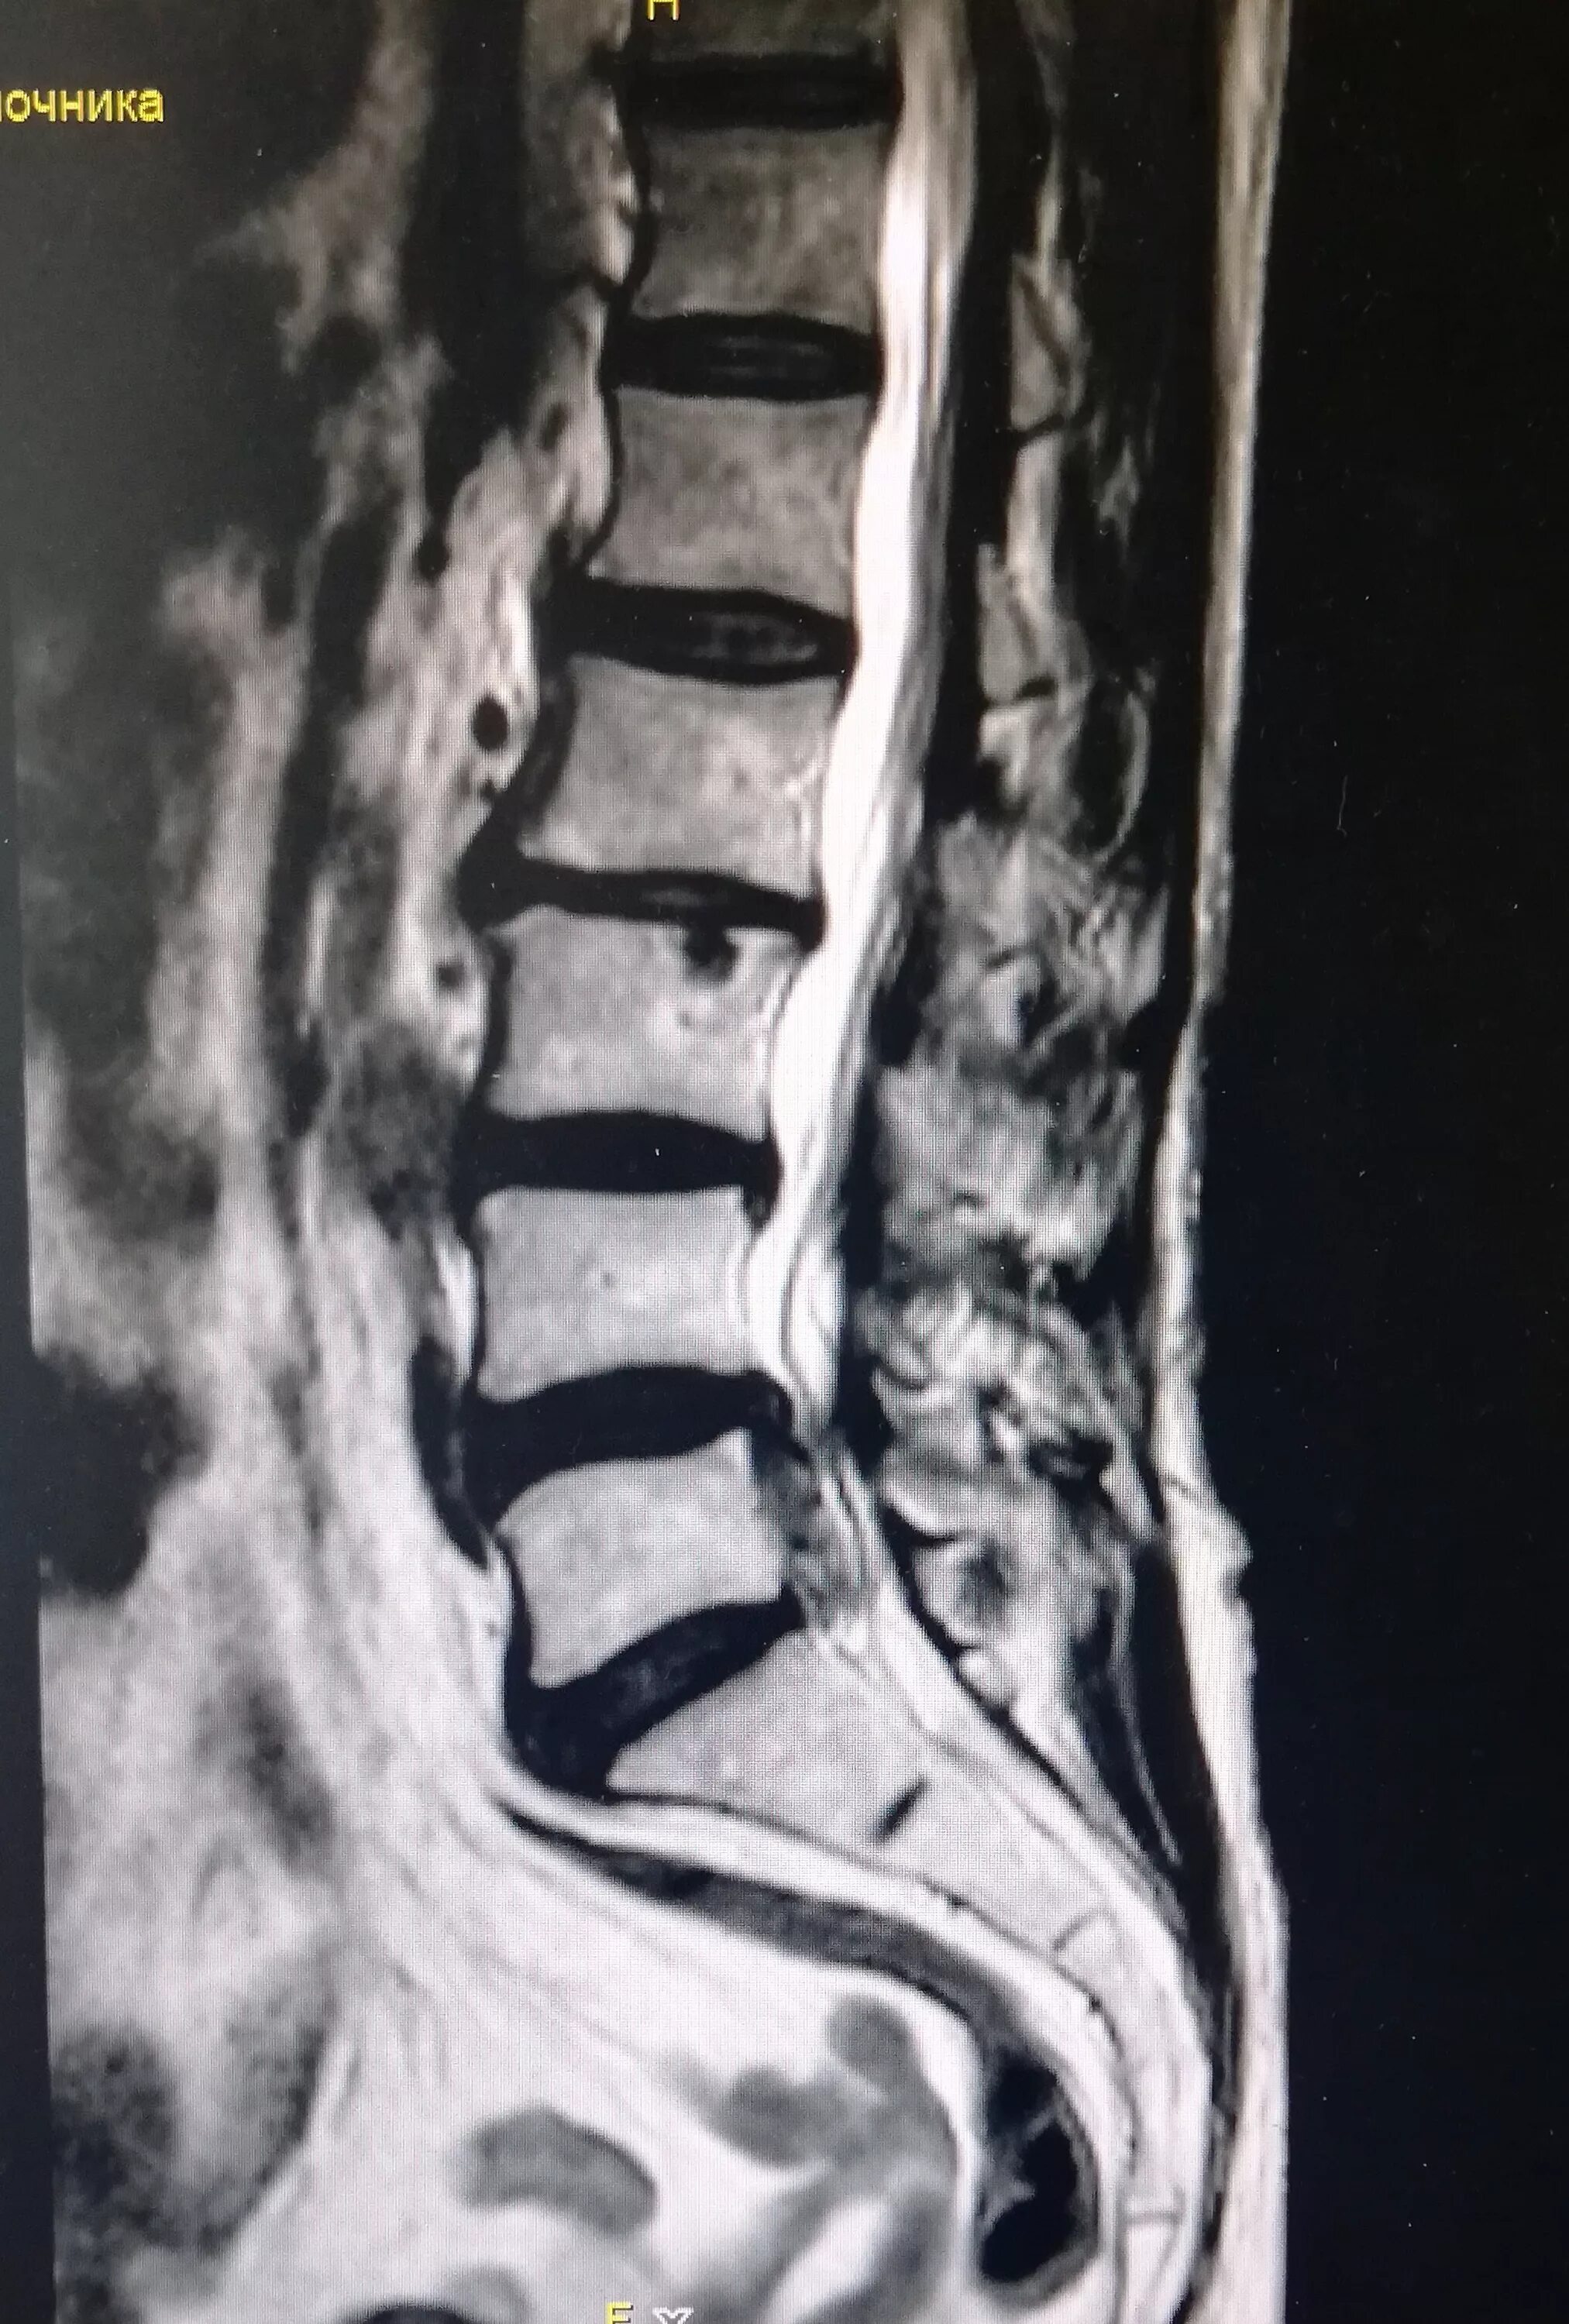

Как выглядит грыжа позвоночника на мрт